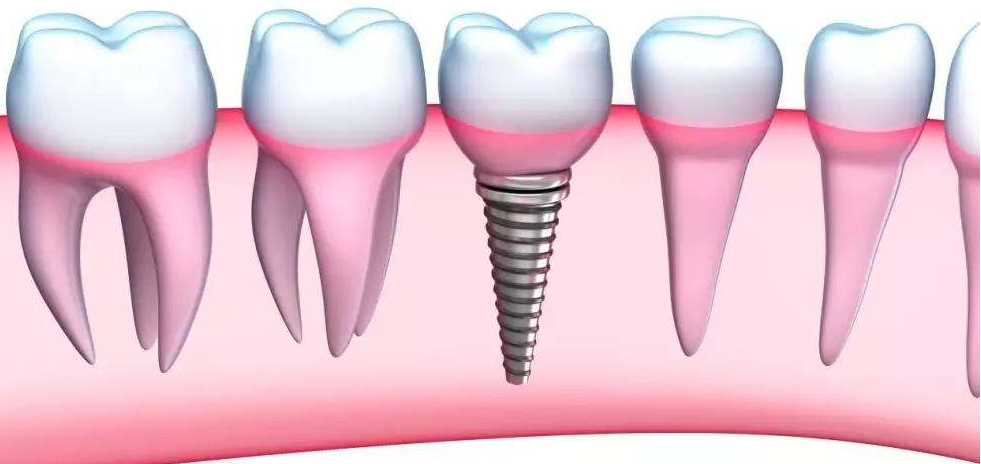

在医生的建议下,他摘下了活动假牙,换做种植牙。医生考虑到他牙槽骨骨量不足,做传统种植的话需要3~6个月甚至更长时间,就采用All-on-4种植牙修复技术。

不一定要缺一颗种一颗做全口种植,特别是牙槽骨量不足的患者,其实可以选择All-on-4种植牙修复技术,只需植入上下各4颗种植体,就能重建全口牙齿。》》》推荐阅读:老年人保护牙齿很重要,千万不要这样做

这种方式的种植体呈30~45°倾斜,增大骨骼与种植体的接触面,避开了上颌窦和下齿槽神经管等重要解剖结构,有的牙槽骨骨量不足也可以不用做植骨手术。

种植牙修复的效果可媲美真牙,减少了种植体的植入,避免了大量的植骨,还降低种植手术的创伤和风险,更重要的是在植入后患者即可戴上临时牙冠,恢复咀嚼功能,避免了3~6个月的无牙等待时间。

但另一方面,All-on-4种植牙技术对医生的技术水平要求极高,同时依赖高精度的口腔设备进行检测。“如果医生种植得过浅,就容易导致种植后牙齿松动;如果医生种植得过深,又可能伤及神经等。”